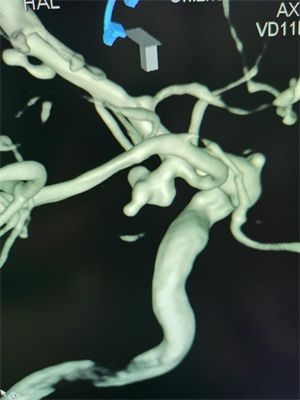

△图一:手术前可见后交通动脉瘤合并多个突起

△图二:手术后动脉瘤已经栓塞,造影不可见